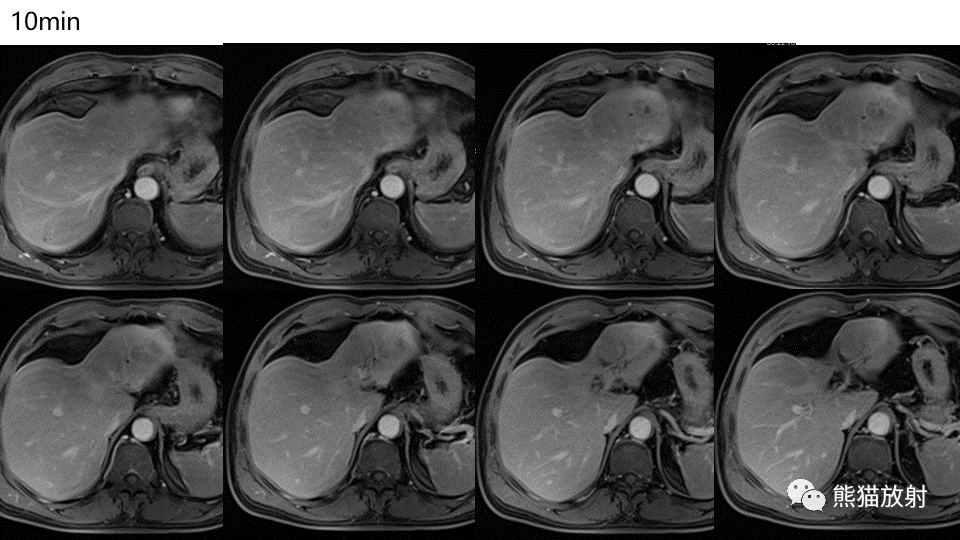

【PPT】肝内胆管细胞癌 VS 肝脓肿